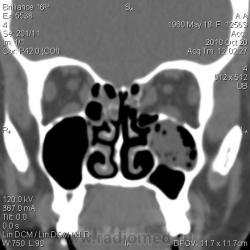

КТ. Нагноение кисты верхнечелюстной пазухи.

Женщина 30 лет, жалобы - головная боль, направлена для уточнения характера патологии ППН. Снимков пазух у меня нет.

Отграничено, ровный контур, гнойная (30 ед.Н) плотность

Да, надо признать, что уважаемая Людмила Григорьевна всегда старается объяснить, что не понятно коллегам. Но, я порассуждал с точки зрения «банальной эрудиции». Эта перегородка, в гайморовой полости, о чем свидетельствуют сканы, не полностью разделяет гайморову пазуху на две «изолированные полости», и сообщение между «разделениями» весьма не хилое есть, и если, предположить, что «то» сопли, то сопли, как всякая жидкая или полужидкая субстанция обязательно с учетом силы тяжести протекли вниз, чего не произошло, а, следовательно, процесс является, чем – то ограниченным, и имеющим определенную оболочку.

плотность. Есть серая шкала, от черного (воздух) до белого (кость). Остальное - оттенки серого. Я подобрала режим для демонстрации, чтоб наиболее выигрышно показать и пазуху, и ее содержимое. В данном случае больше вероятность за нагноение кисты: пузырьки газа, гнойная плотность патологического содержимого. Более жидкая субстанция растеклась бы, а полип имеет большую плотность (40-60 единиц). Было бы интересно проследить динамику, но пациентка категорически отказалась от пункции, так что вероятнее всего, что история на этом и закончится. А ППН можно и на животе делать с запрокидыванием головы назад - только для пациента не очень удобно, а при шейном остеохондрозе иногда и невозможно.

Без сомнений это острый процесс (гайморит), слизистая  клеток решетчатой кости тоже  неравномерно утолщена.